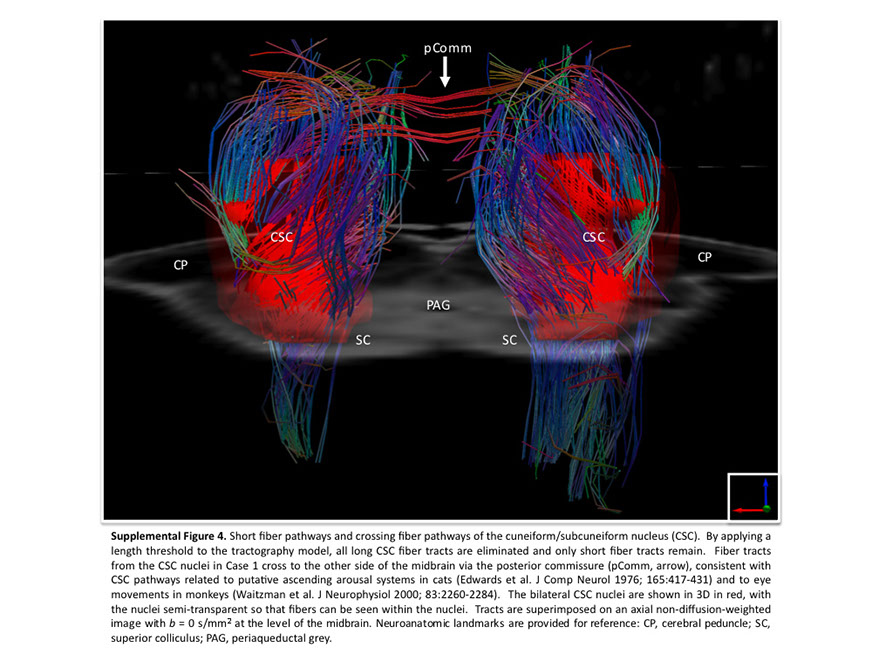

Many observations suggest that CFS could derive from residual damage to the reticular activating system (RAS) of the upper brain stem and/or to its cortical projections. It should be pointed out that although the larger right greater than left asymmetry in regional cerebral blood flow is found at the parietotempotal level in CFS patients as compared to healthy controls, no significant correlations are found between frontal tracer uptake and right-left parietotemporal asymmetry, on the one hand, and clinically relevant CFS dimensions on the other. Damage to the RAS could be produced by a previous viral infection, leaving functional defects unaccompanied by any gross histological changes.

In this respect, fluorine-deoxyglucose positron emission tomography showed specific metabolism abnormalities in CFS patients (hypometabolism in right mediofrontal cortex and brainstem) as compared with both healthy controls and depressed patients. The most relevant abnormality is brain stem hypometabolism, which has been also reported in single-photon emission computed tomography studies and seems to be a marker for the in vivo diagnosis of CFS